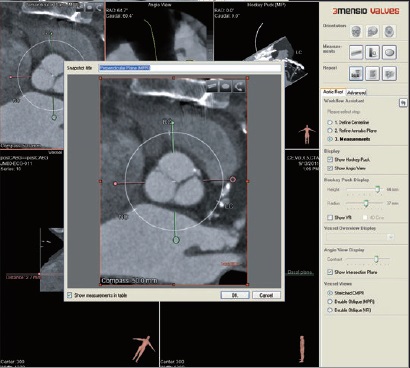

Програмне забезпечення MM Roadmap (або Multi-modality fusion) забезпечує додаткову інформацію завдяки 3D-візуалізації судинної анатомії, що успішно використовується при плануванні та навігації транскатетерної заміни клапану для лікування вроджених вад серця.

MM Roadmap дозволяє суміщувати 2D-флюороскопічні зображення з раніше отриманим 3D-об’ємом. Це може бути КТ або МРТ об’єм при чому незалежно від виробника сканера, або з ангіографічної системи Canon.

Суміщене зображення на моніторі змінюватиметься синхронно в залежності від нахилу С-арки, зміни SID, поля огляду, висоти та положення деки столу.

Можливість використання програмного забезпечення MM Roadmap під час складних втручань допомогає скоротити тривалість опромінення та об’єм введеної контрастної речовини..